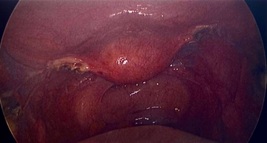

8:35am Tissue delivered with EndoCatchTM via umbilicus port. Bilateral salpingo-oophorectomy complete (Figure 8).

Figure 8: After Bilateral Salpingo-Oophorectomy